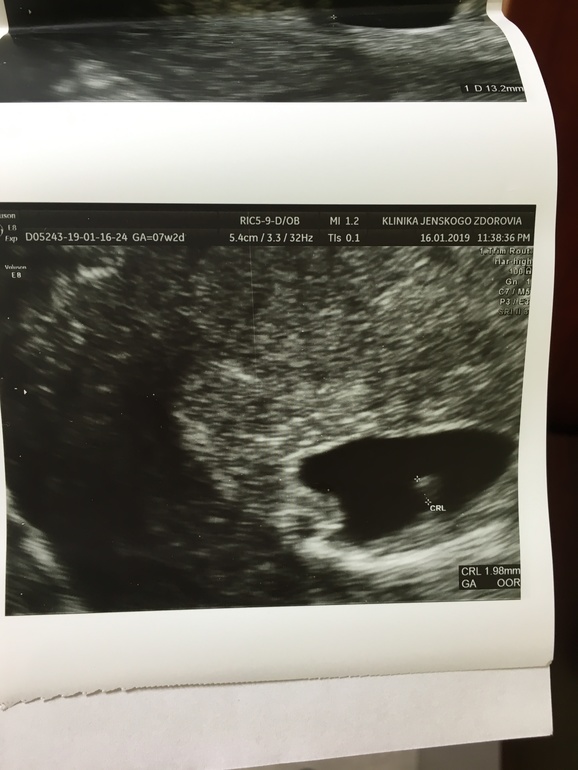

Можно ли называть эмбрион не живым, если отмечается рост ктр. В моем случае, в четверг ктр был 1,98 мм, а в субботу 4,1 мм. Но при этом не было с/б. Как возможен рост при отсутствии с/б?

ПЯ тоже выросло в размерах за это время, но началась его деформация. И возможно ли сохранить Б при наличии деформации пя?

В чт УЗИ делала в клинике платной на хорошем аппарате и мы заметили сердцебиение, но не могли поймать его, чтобы послушать. А второе УЗИ делали в больнице на древнем аппарате и ктр замерили и он увеличился, а с/б не увидели.